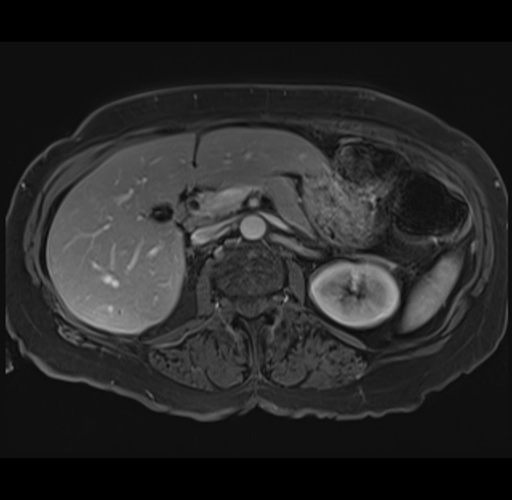

MRI T1